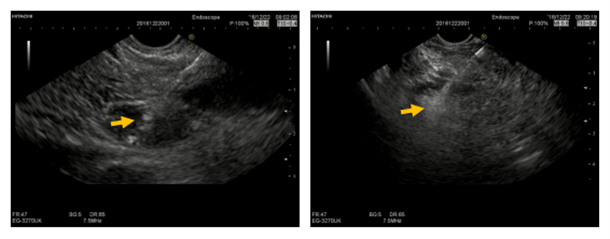

消融4日后复查超声内镜后表现为中等偏高回声病灶,血管消失